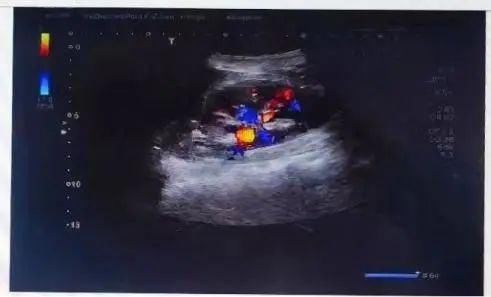

贾女士的输尿管结石位于输尿管膀胱开口处,大小约14mm*7mm,未与输尿管黏膜粘连,为快速碎石创造了有利条件。

贾女士结石影像